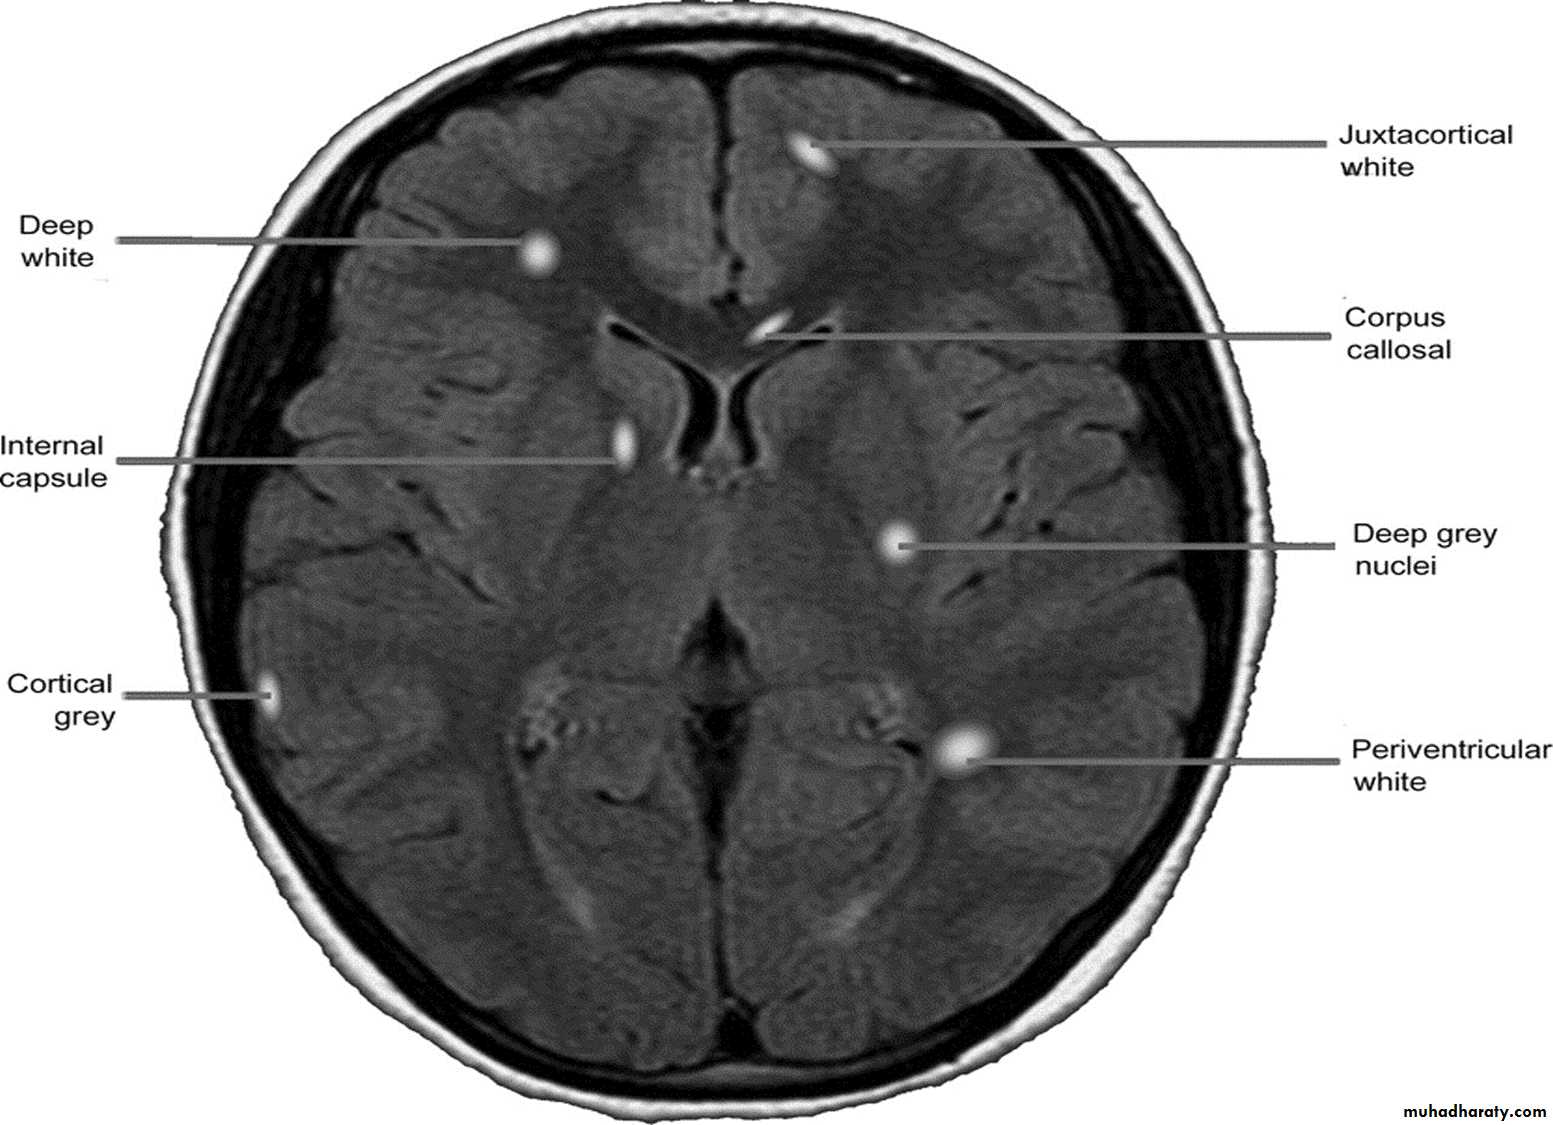

MRI :characteristic abnormalities are found in >95% of patients, although more than 90% of the lesions visualized by MRI are asymptomatic

Lesions are frequently oriented perpendicular to the ventricular surface,(Dawson’s fingers)

Lesions larger than 6 mm located in the corpus callosum, periventricular white matter, brainstem, cerebellum, or spinal cord are particularly helpful diagnostically